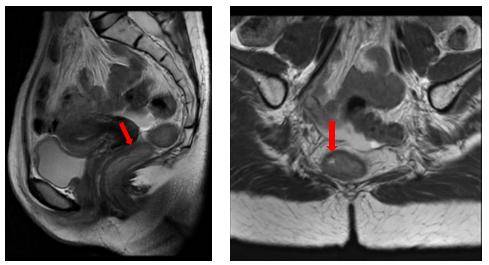

2024年10月28日直肠MR:直肠下段癌,T2N1b 17。病变长27mm,下缘距肛50mm,累及3/4周径,位于腹膜反折下方。可见直肠系膜内、双侧髂外血管旁小淋巴结。MRF-, EMVI-。

2025年1月3日直肠MR:直肠下段癌范围较前缩小,直肠系膜内小淋巴结较前缩小。MRF-,EMVI-,肛管未见受累。

影像学:2025年4月24日直肠超声造影考虑uCR。2025年4月27日直肠MR考虑治疗后改变,直肠系膜内小淋巴结和双侧髂外血管旁小淋巴结,较前相仿。2025年4月26日CT示,左肺上叶新发结节较前明显缩小(4mm→2mm)。

2025年7月29日MR复查:直肠下段稍增厚、肿胀,考虑治疗后改变,较前相仿。

2025年10月22日MR复查:直肠下段稍增厚、肿胀,考虑治疗后改变,较前相仿。